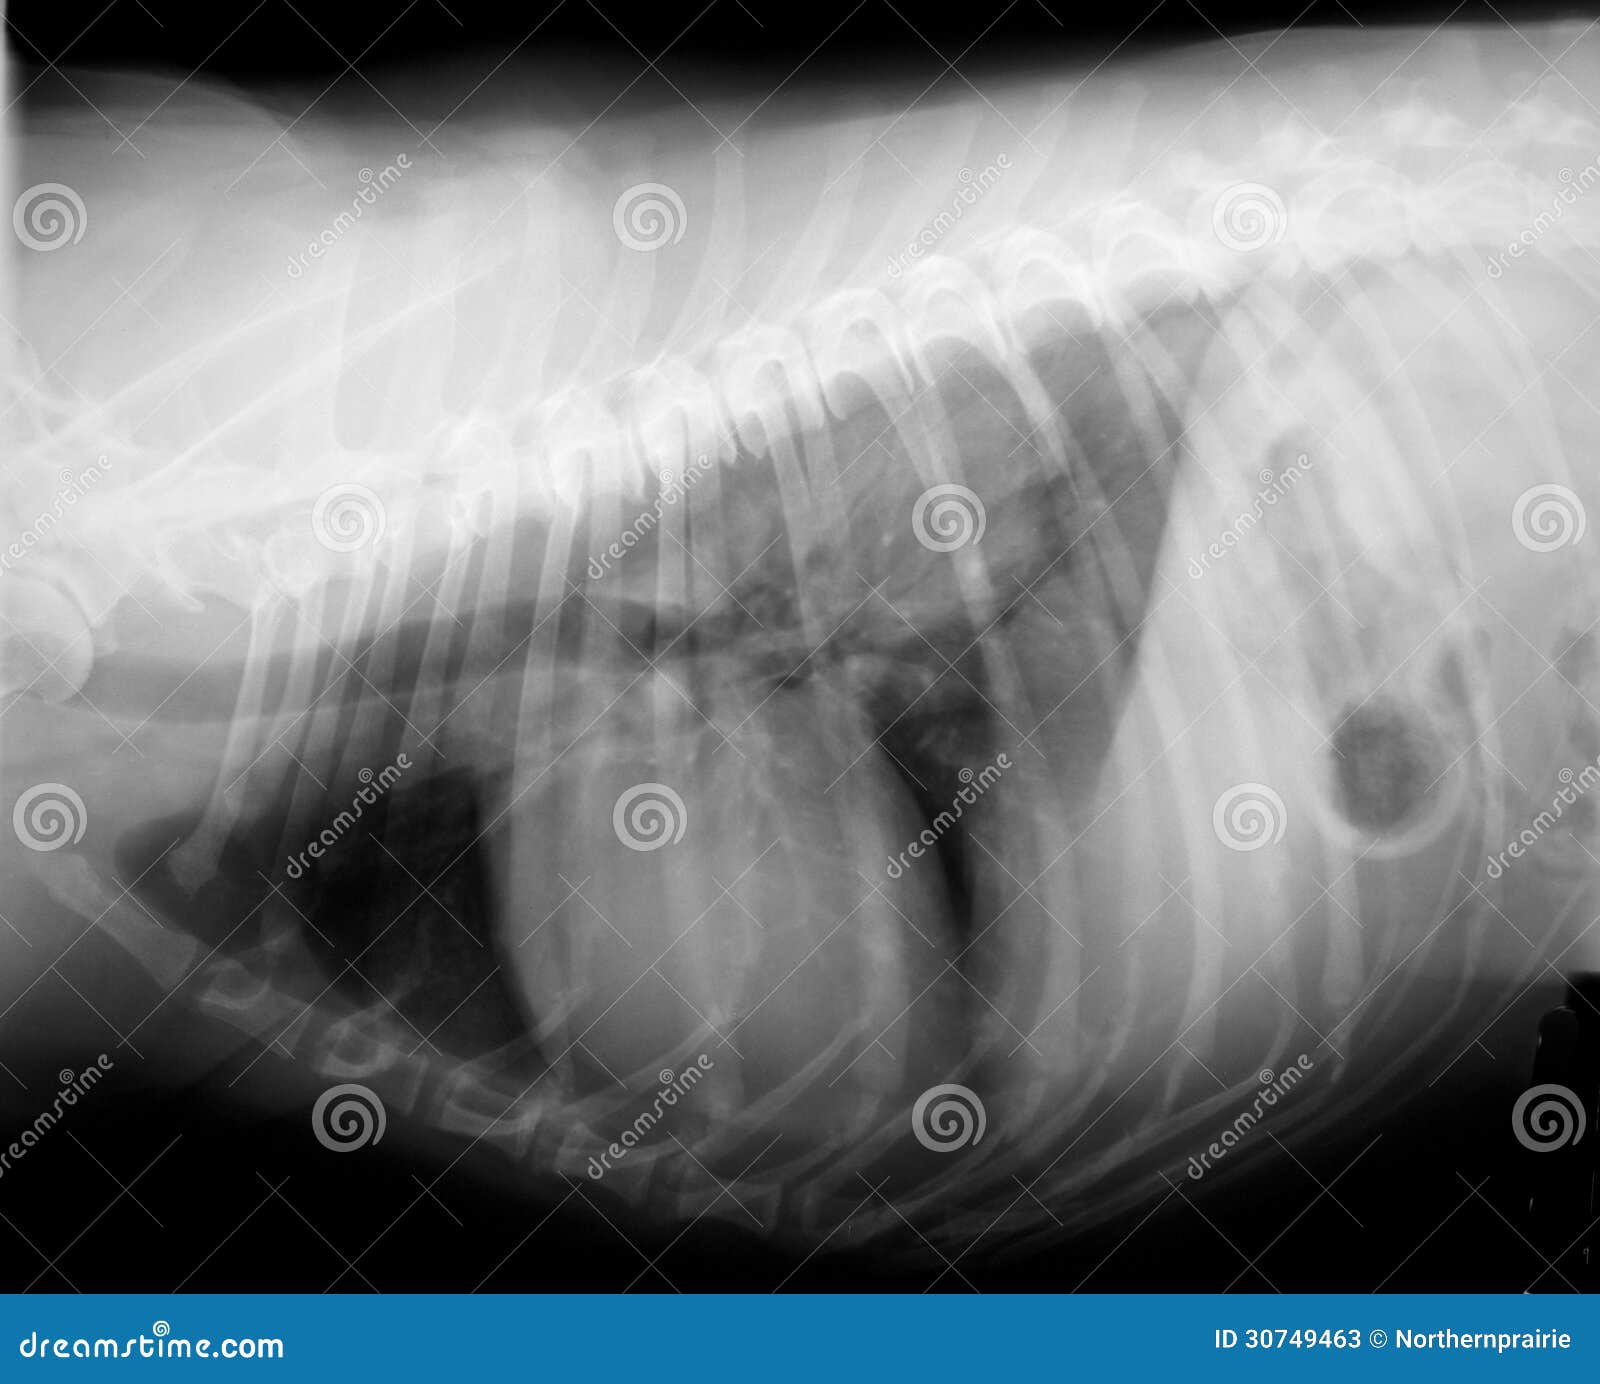

В клинике собаке сделают рентген, который подтвердит или опровергнет отек легких, а также проведут осмотр собаки, прослушают ее и выполнят ряд лабораторных исследований.

Для диагностики отека легких у собак используются такие методы, как аускультация, рентгенография грудной клетки или ультразвуковое исследование, также требуется анализ крови. Электрокардиограмма, анализ мочи и измерение кровяного давления — другие важные тесты, позволяющие выяснить, есть ли у вашей собаки отек легких.

Если состояние вашего питомца стабильное, можно выполнить рентгенографию грудной клетки, положив собаку на спину. На этой рентгенограмме могут быть признаки отека легких, такие как повышенная интерстициальная или альвеолярная непрозрачность. У собак, страдающих кардиогенным отеком легких, также могут наблюдаться кардиомегалия и расширенные легочные вены.

Рентгеновские снимки являются основным инструментом для диагностики отека легких, поскольку они выявляют жидкость внутри легких собаки. Рентген также может выявить увеличенное сердце или другие аномалии сердечной мышцы.